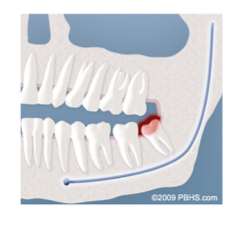

Infección:

El problema clínico más frecuente que vemos es la pericoronitis (una infección localizada de las encías). Sin suficiente espacio para una erupción total, el tejido de las encías alrededor de la muela del juicio puede irritarse e infectarse, lo que resulta en dolor recurrente, hinchazón y problemas para masticar y / o tragar.